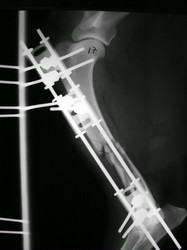

PRÁCTICAS CURSO DE FIJACIÓN EXTERNA PERFECCIONAMIENTO.

Húmero.